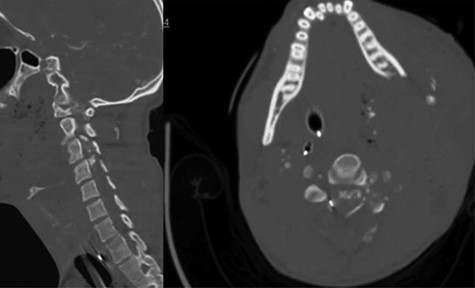

A 24-year-old African–American male presented with a gunshot wound through the left face and neck. On exam the patient was noted to be pulseless and apneic. After resuscitation, initiation of a mass transfusion protocol and return of spontaneous circulation, the patient was GCS 11 (E4V1TM6) and was noted to have no movement in any extremities. A computed tomographic (CT) cervical spine scan and CT angiography of the neck revealed a bullet trajectory through the left C2–3 facet with fractured c3 posterior elements and a bullet fragment at the C3 level, a left vertebral artery dissection, and left internal and external carotid artery transections (Fig. 1). The patient underwent an emergent tracheostomy, neck exploration, left ICA/ECA ligation and partial wound closure. This was followed by endovascular embolization of the left vertebral artery. The patient was noted to have serosanginous drainage from the neck wound consistent with a CSF leak. After an unsuccessful trail of conservative management, a lumbar drain was placed and confirmed with fluoroscopic guidance without CSF egress. A magnetic resonance imaging (MRI) scan of the cervical spine was obtained which demonstrated a pronounced CSF fistula and a complete obstruction of the CSF space at the C3–6 levels (Fig. 2).

CT angiogram of the neck demonstrates a bullet trajectory through the left C2–3 facet with fractured c3 posterior elements and bullet and bony fragments within the canal at the C3–4 level; left: sagittal view; right: axial view.